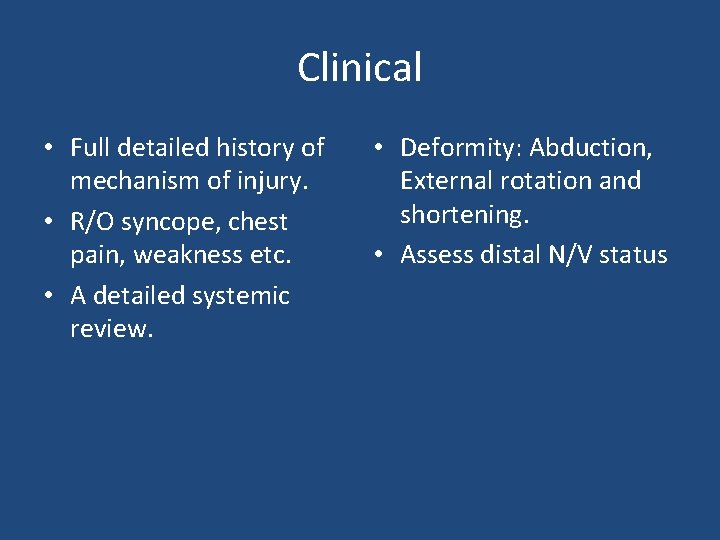

Clinical • Full detailed history of mechanism of injury. • R/O syncope, chest pain, weakness etc. • A detailed systemic review. • Deformity: Abduction, External rotation and shortening. • Assess distal N/V status